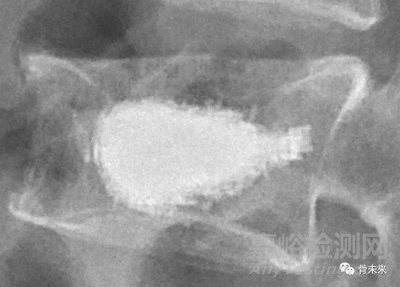

凱利泰囊袋擁有直型、彎型、單管、雙管不同結(jié)構(gòu)形式,其中彎型囊袋是國內(nèi)首個獲批的可彎類囊袋產(chǎn)品。

彎型囊袋區(qū)別于傳統(tǒng)直囊袋,其憑借囊袋囊體前端彎曲的設(shè)計結(jié)構(gòu)可配合凱利泰彎角椎體成形系統(tǒng),在放置進入椎體時,沿彎曲狀通道更容易到達椎體對側(cè)區(qū)域,可在椎體中部區(qū)域平行擴張囊袋,在椎體中部填充骨水泥。彎型囊袋產(chǎn)品無需過大內(nèi)傾角既可滿足手術(shù)需求,可避免使用傳統(tǒng)直型囊袋產(chǎn)品單側(cè)入路穿刺椎弓根時,內(nèi)傾角過大則增加脊髓損傷和硬膜出血的風(fēng)險。